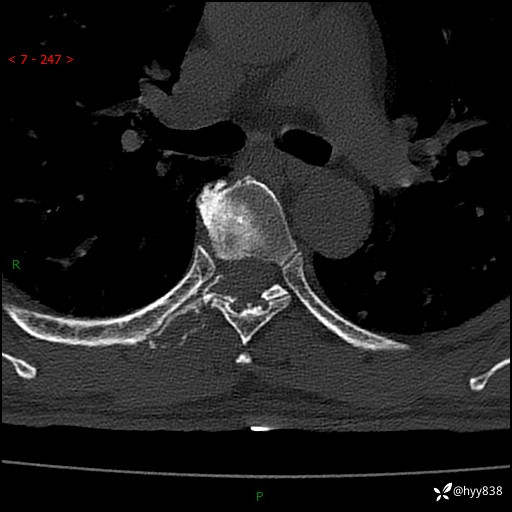

胸椎CT平扫(骨窗+软组织窗)